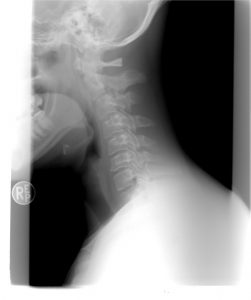

Obecnie wiele osób boryka się z dokuczliwym bólem karku oraz szyi. Aby skutecznie uporać się z tak nieprzyjemnymi dolegliwościami doskonałym pomysłem jest zastosować bardzo łatwe w wykonaniu ćwiczenie opatentowane przez niemieckiego lekarza Rolanda Brachta. Największą zaletą tego ćwiczenia stanowi fakt, że niemalże natychmiastowo redukuje ono napięcie w odcinku szyjnym.